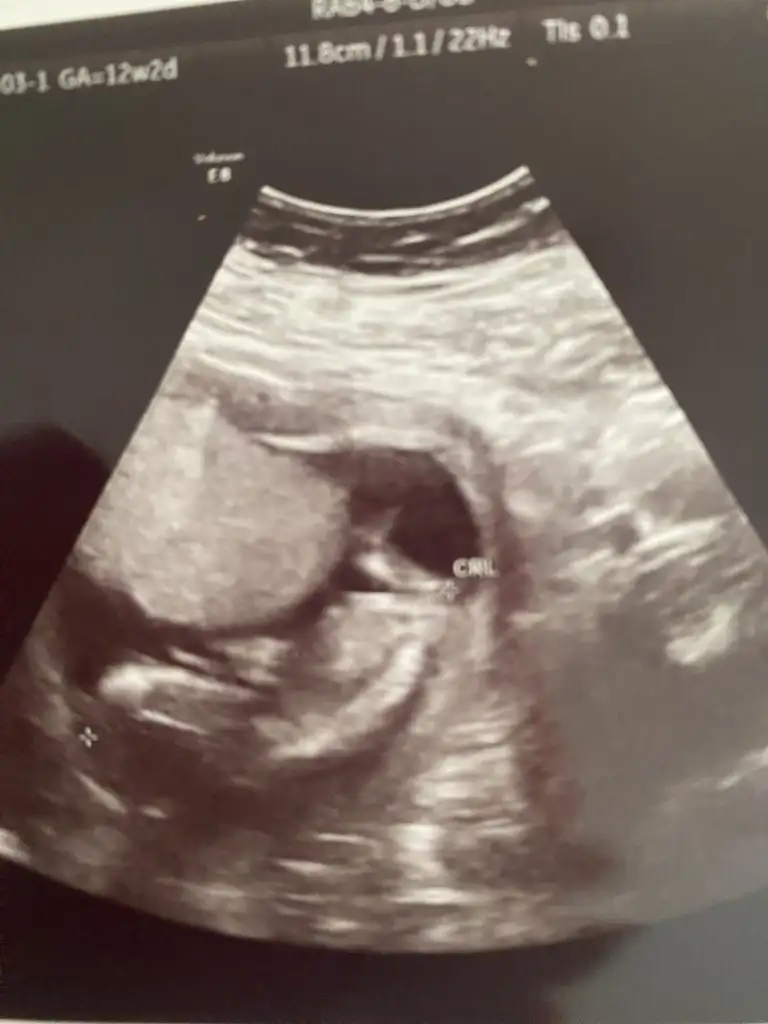

Kızlar 12+2 den merhaba bizde tahmin istiyoruzzz 🫶

• 3588652D-98B5-4025-87F9-DBBE0233345C.webp

3588652D-98B5-4025-87F9-DBBE0233345C.webp

19,5 KB · Görüntüleme: 37